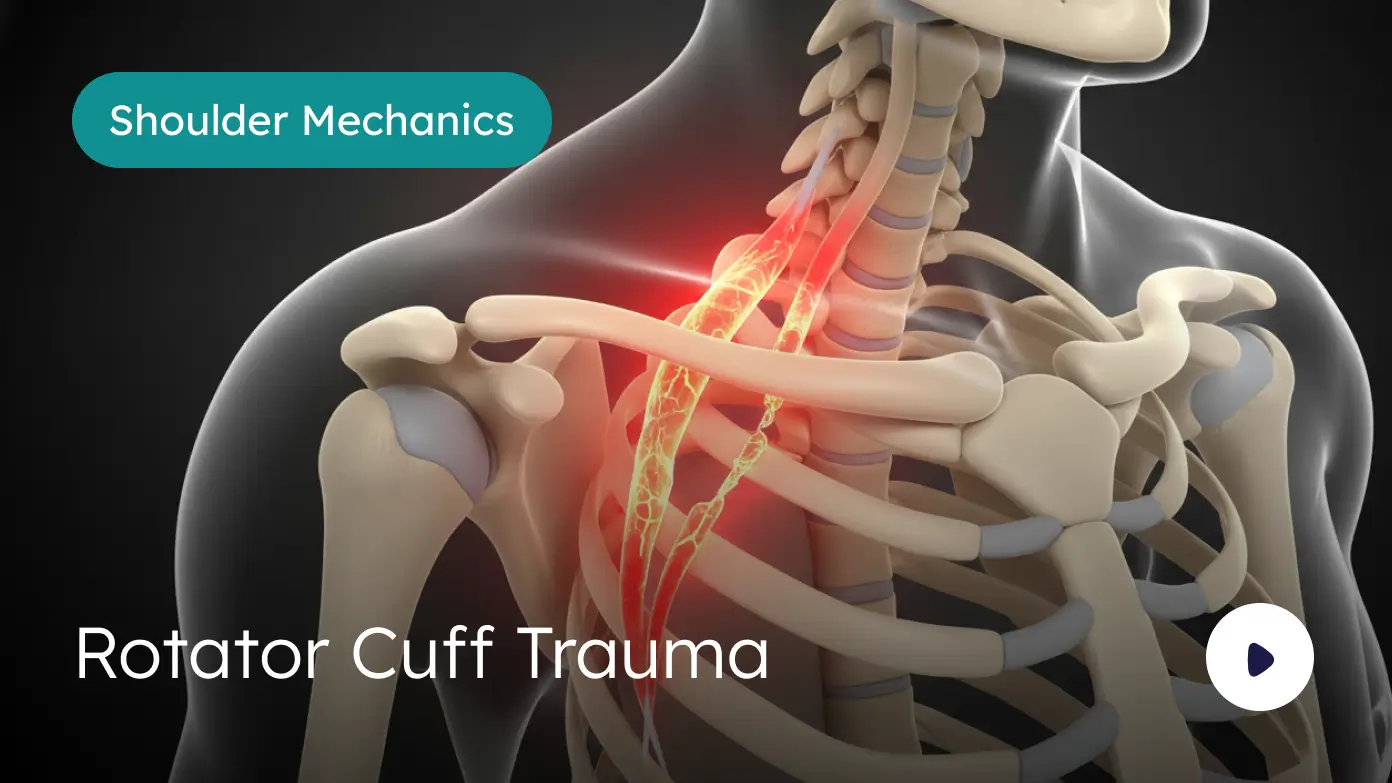

Explore Video Library

Comprehensive educational content covering orthopaedic surgery, regenerative medicine, peptide therapy, and evidence-based rehabilitation protocols.